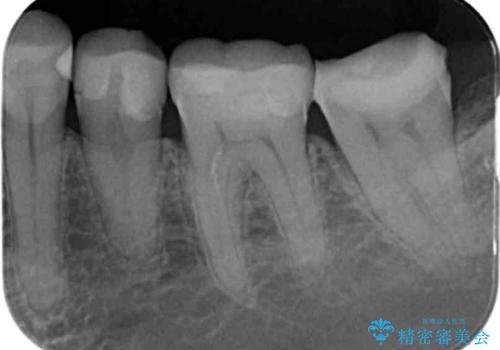

昔いれたクラウンが割れたので金属の被せ物を入れたいの症例写真

昔いれたクラウンが割れたので金属の被せ物を入れたい